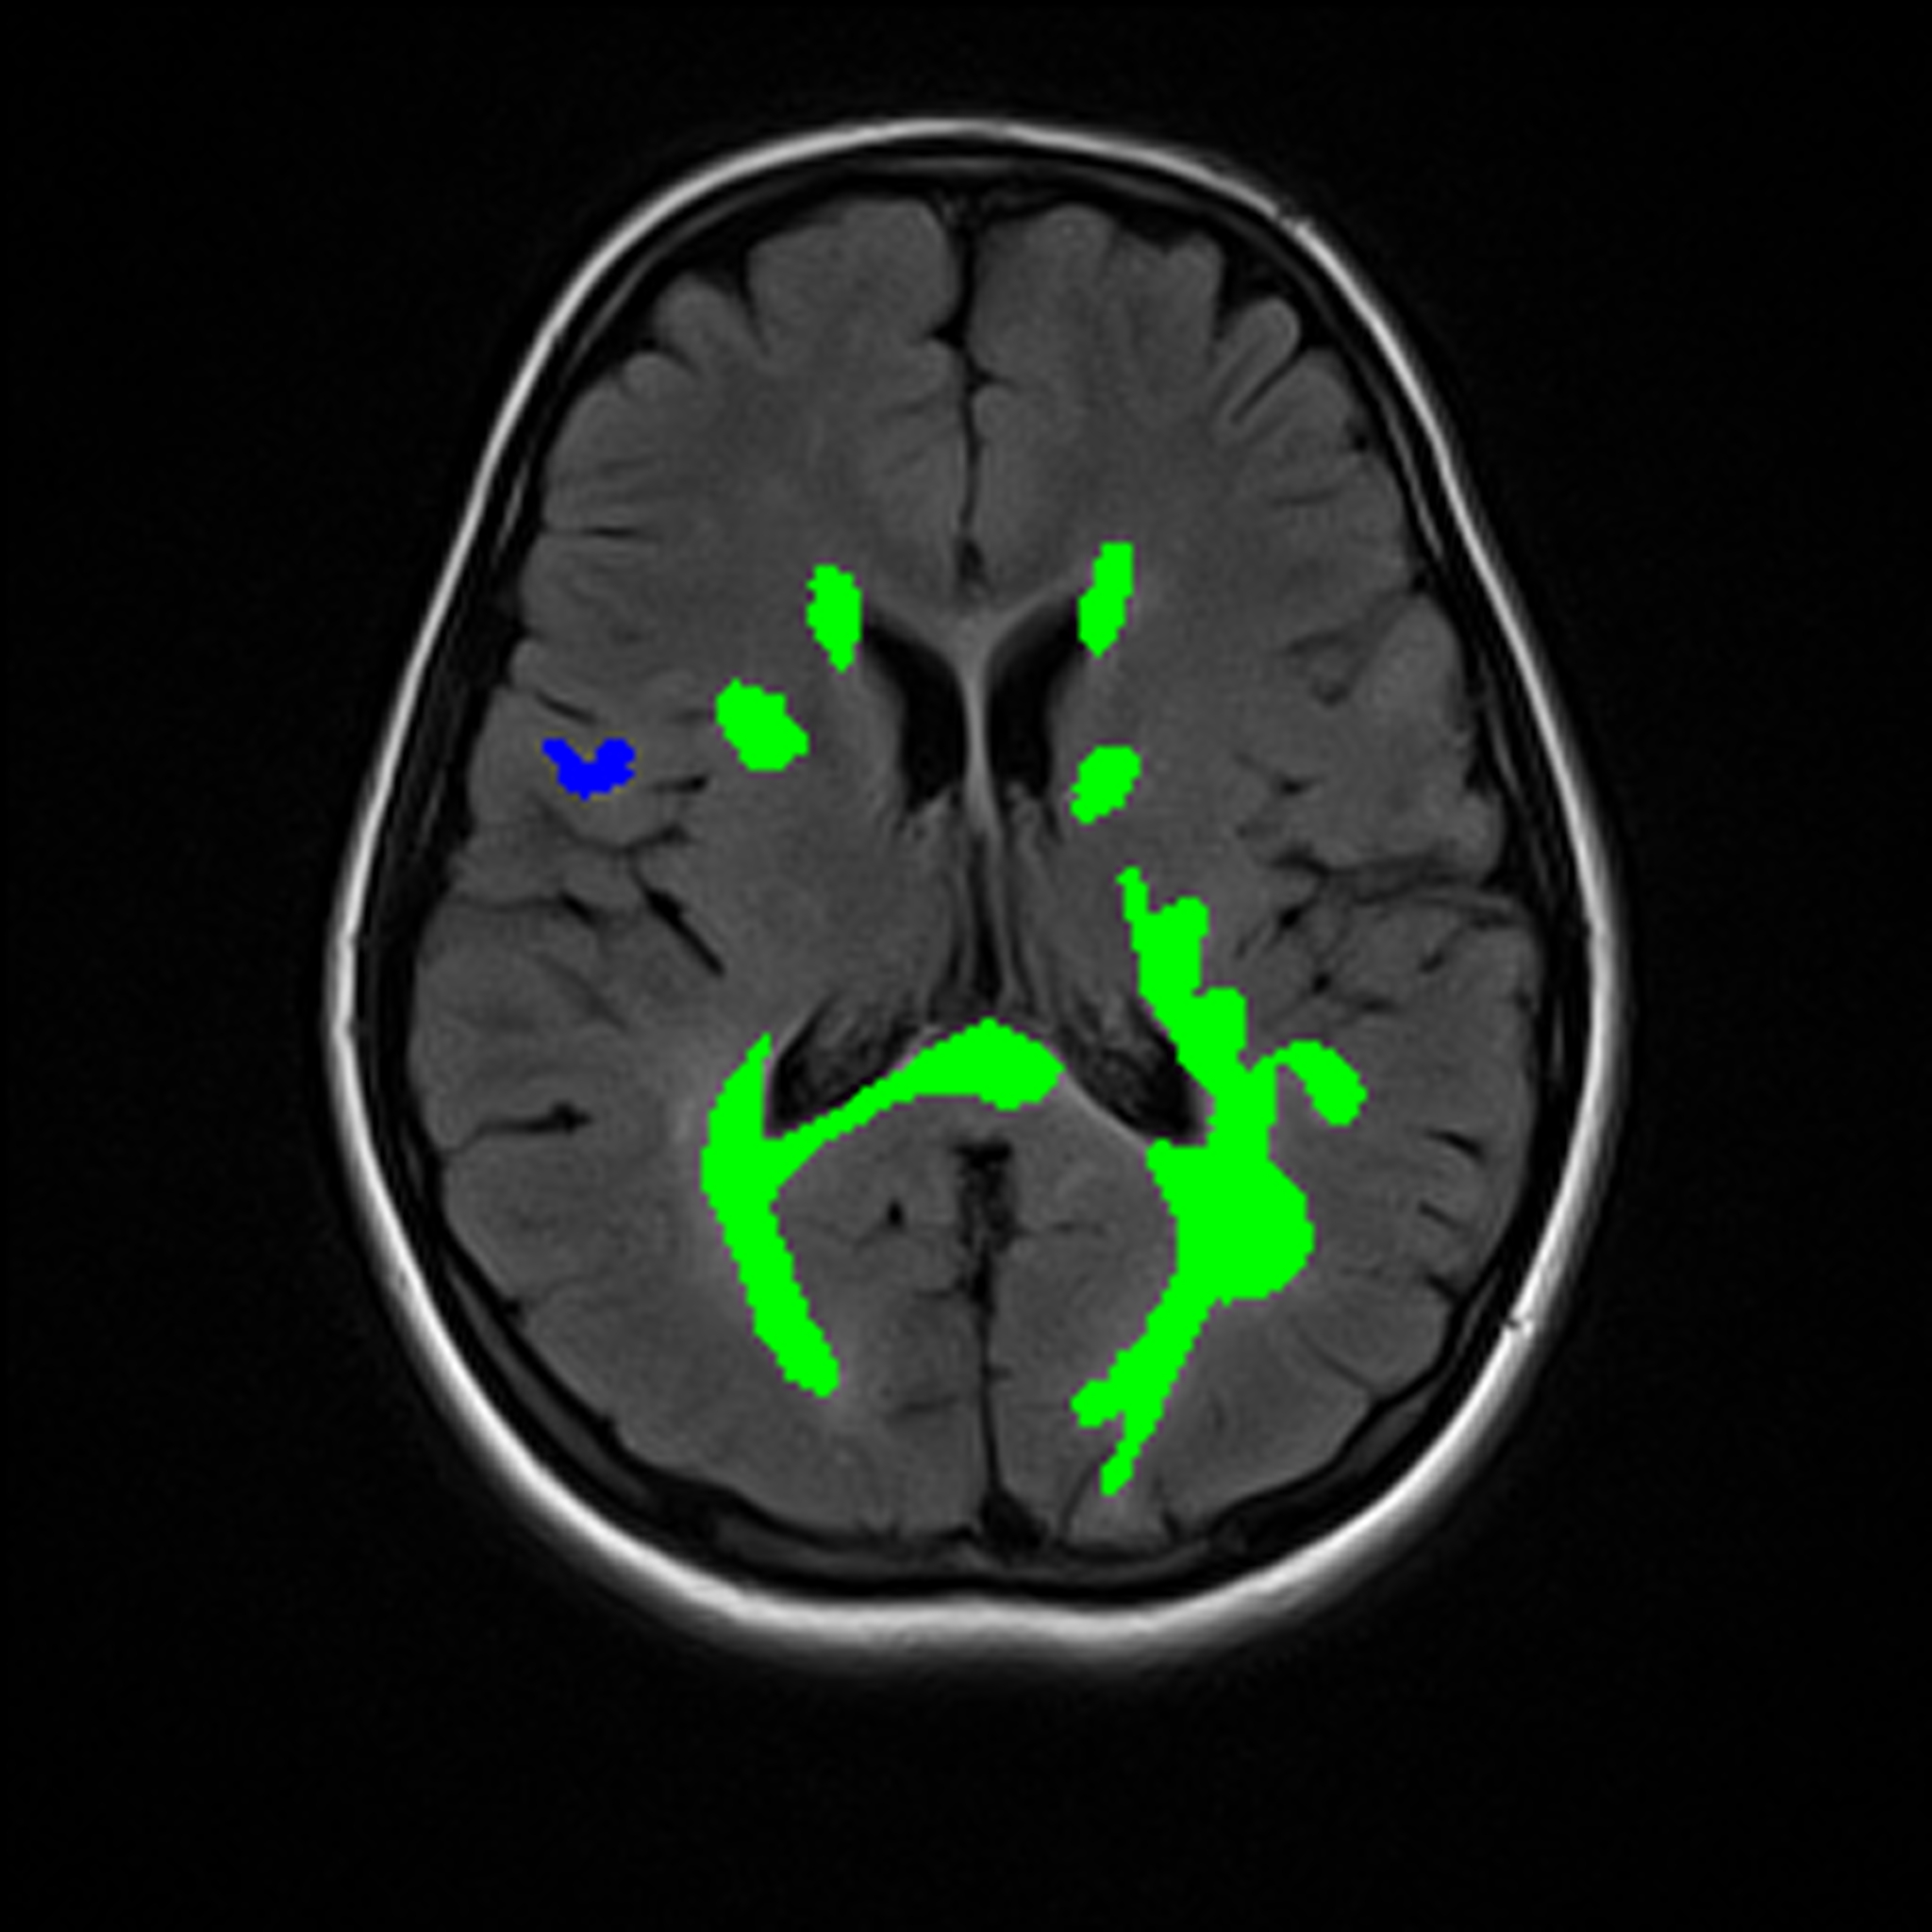

MRI

FLAIR

Segmentation

Multiple Sclerosis

MS Lesion Segmentation: AI-Powered Multi-Class Lesion Mapping in MRI.